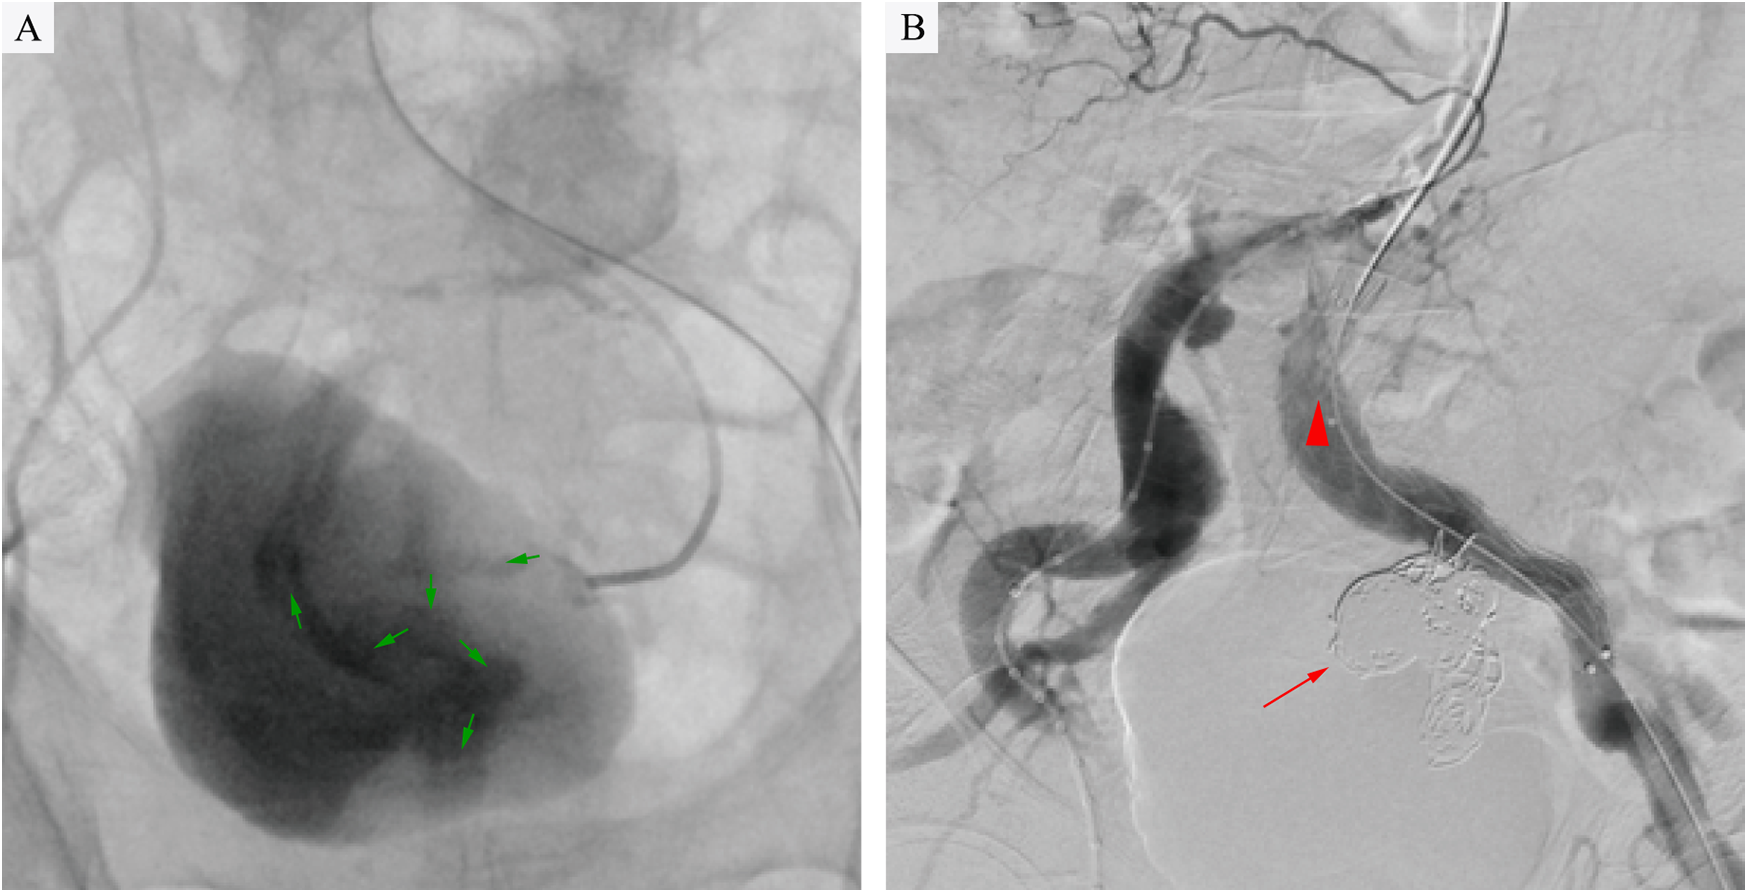

A multidisciplinary team comprising specialists in vascular surgery, anesthesiology, gastrointestinal surgery, and gastroenterology, in conjunction with the patient's family's preferences, concluded that endovascular intervention by vascular surgery was necessary given the patient's hemorrhagic shock and severe comorbidities. The procedure was performed as follows: after local infiltration of lidocaine to both groins, the common femoral arteries were accessed bilaterally. Two Perclose ProGlide™ devices (Abbott Vascular, CA, USA) were pre-deployed in the left common femoral artery, followed by insertion of a 12F sheath (Cook Medical). Through a 5F sheath on the right, a pigtail catheter was advanced to the infrarenal aorta, where angiography demonstrated bilateral common iliac artery aneurysms and a left internal iliac artery aneurysm. Using a crossover technique, a catheter was positioned in the left common iliac artery to obtain roadmap guidance. It was then selectively advanced into the aneurysm sac. Hand-injected angiography revealed the outflow vessel and contrast agent leakage into the rectal colon (Figure 2A). A microcatheter and microwire (Cook Medical) were used to select the outflow vessel, and fibered coils (MicroNester® Embolization Coils: 4mm × 2, 3mm × 5, 2mm × 5) were deployed for complete embolization. The catheter was withdrawn into the aneurysm sac, where additional coils (MReye® Embolization Coils:20mm × 6, 18mm × 4, 12mm × 5,10mm × 3, 8mm × 3) were placed to achieve dense packing. The catheter was further withdrawn to the inflow zone of the aneurysm, where embolization was completed using fibered coils (MicroNester® Embolization Coils: 4mm × 3, 3mm × 4, 2mm × 5). Post-embolization hand-injected contrast via the left sheath showed no opacification of the left internal iliac artery, with preserved flow in the external iliac artery. A covered stent graft (Endurant II 16 × 10 × 156 mm, Medtronic) was deployed from the origin of the left common iliac artery to the mid portion of the external iliac artery. Completion angiography confirmed patency of the left external iliac artery and complete occlusion of the left internal iliac artery (Figure 2B). Postoperative management included parenteral nutrition, blood transfusion, and antibiotic therapy (levofloxacin).

Figure 2

(A) Intraoperative angiography revealed contrast extravasation (green arrows) into the rectal lumen, confirming an internal iliac artery aneurysm-rectal fistula following selective catheterization of the left internal iliac artery aneurysm. (B) Angiography confirmed complete aneurysm exclusion after coil embolization (red arrow) and stent-graft deployment (red triangle), with no residual contrast leakage into the rectum.